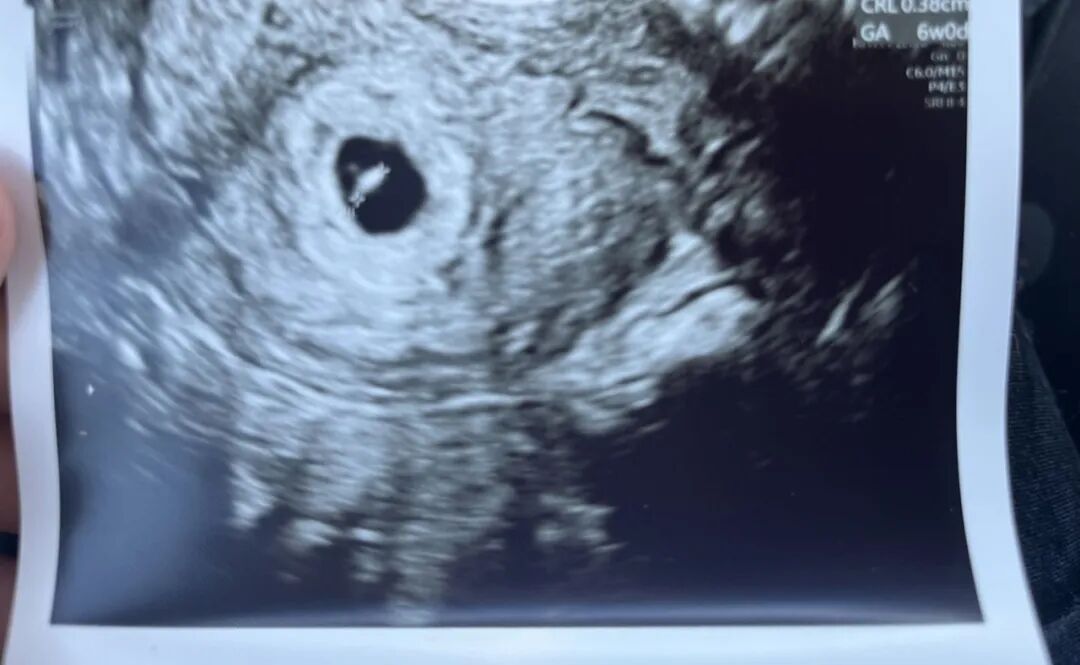

爱妈A在首次B超检查中传来了喜讯,她已经怀孕六周,宝宝成功着床!和她匹配的是一对中年准父母,他们在听到这个消息时无比激动。由于年纪较大和身体条件的限制,自然怀孕对他们来说带来了较高的风险,这使得他们的生育之路充满了挑战。然而通过匹配捐luan女生,以及得到爱妈A的帮助,他们成功制作了优质的胚胎,并且终于迎来了这份长期以来梦寐以求的新生命。